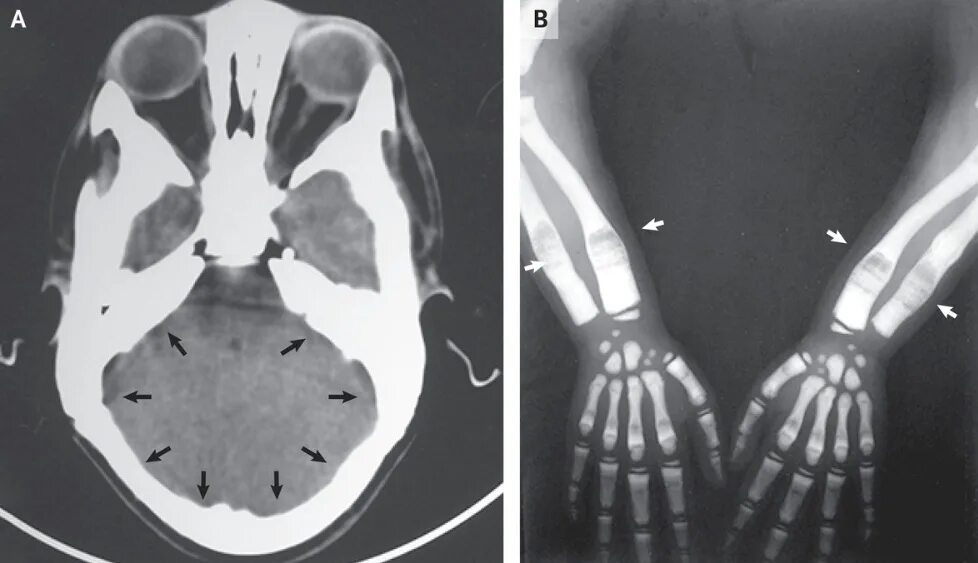

Заболевание кт